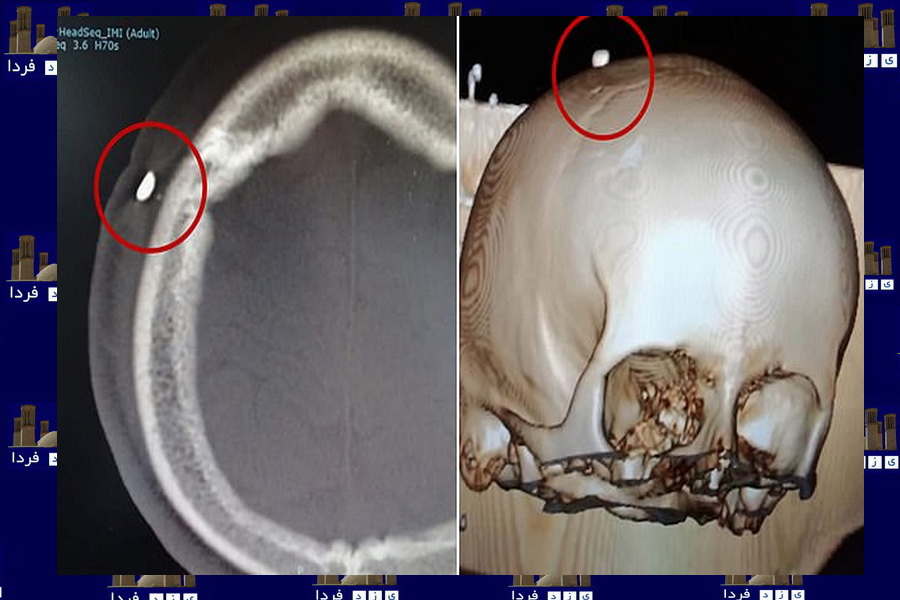

جا ماندن یک دندان در جمجمه پسر 14 ساله پس از گاز گرفتنش در فوتبال+ تصویر